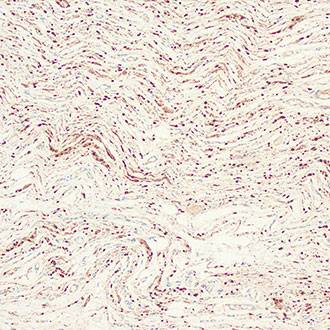

SMA

SMA -